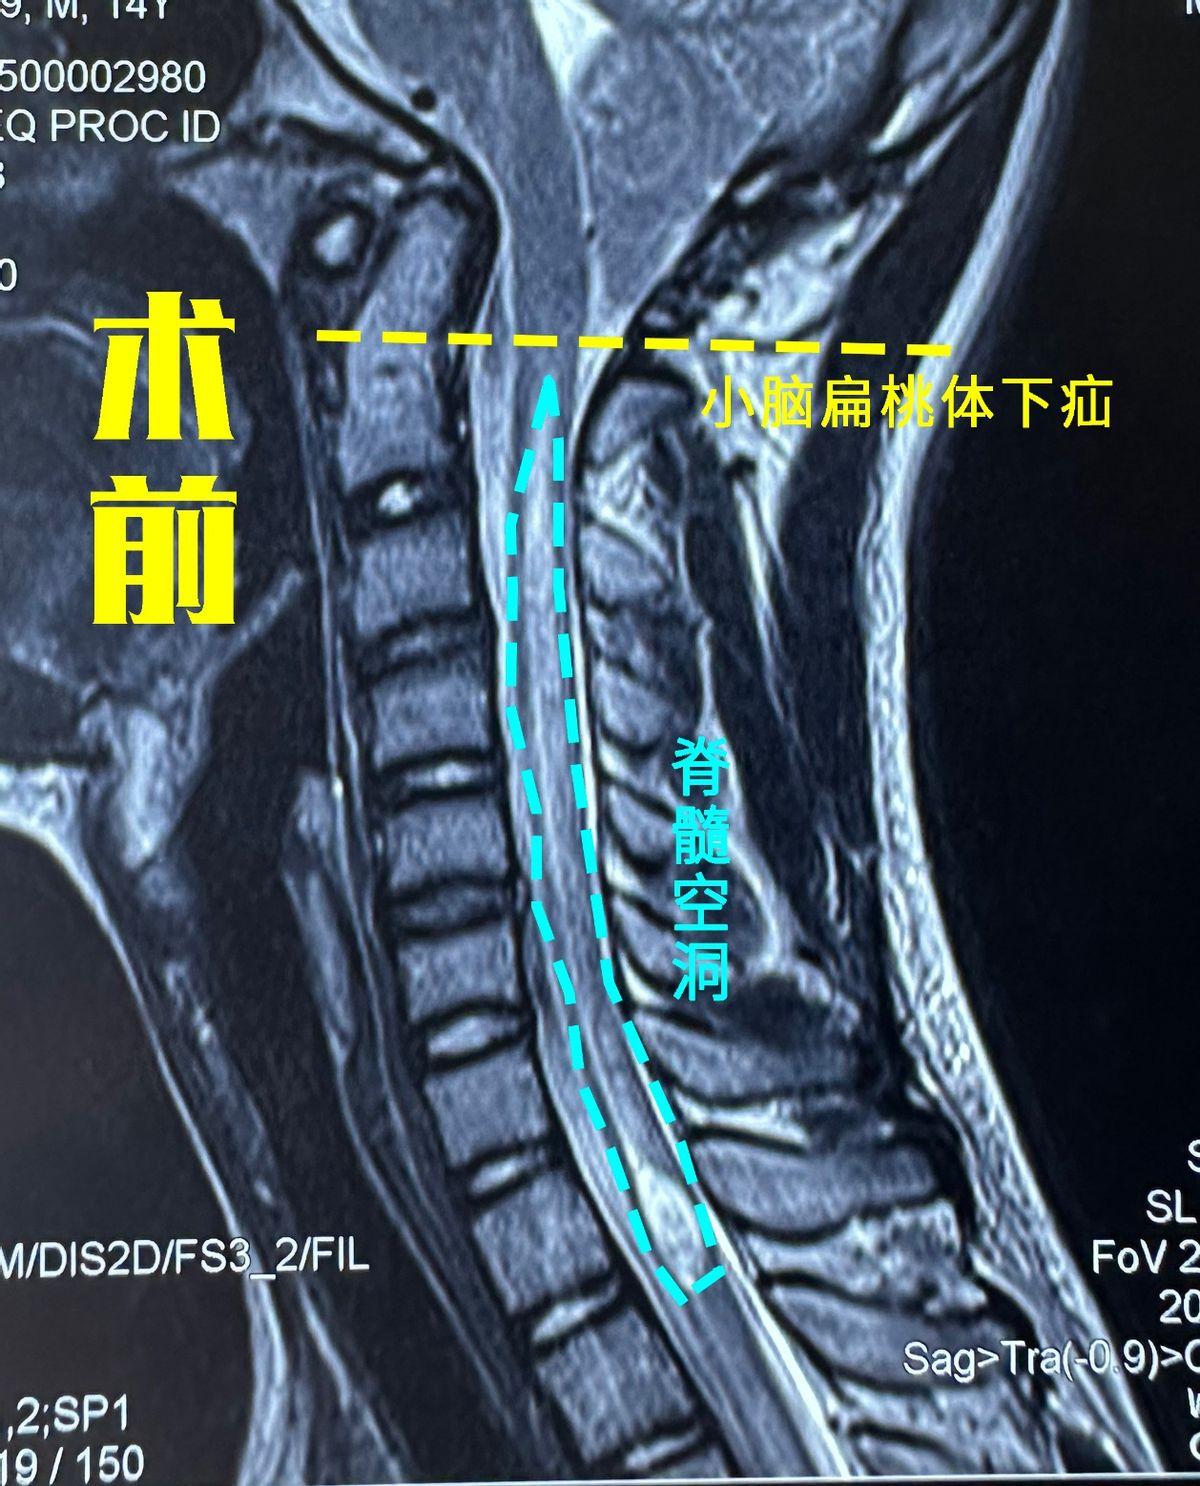

张玉琪:危险的小脑扁桃体疝_枕骨大孔疝_枕骨大孔疝疾病介绍 - 好大夫

当小脑扁桃体向下疝出超过枕骨大孔下缘5mm即可诊断为小脑扁桃体下疝

后颅底肿瘤不但引起头痛,呕吐等高颅压症状,严重者诱发枕骨大孔疝等